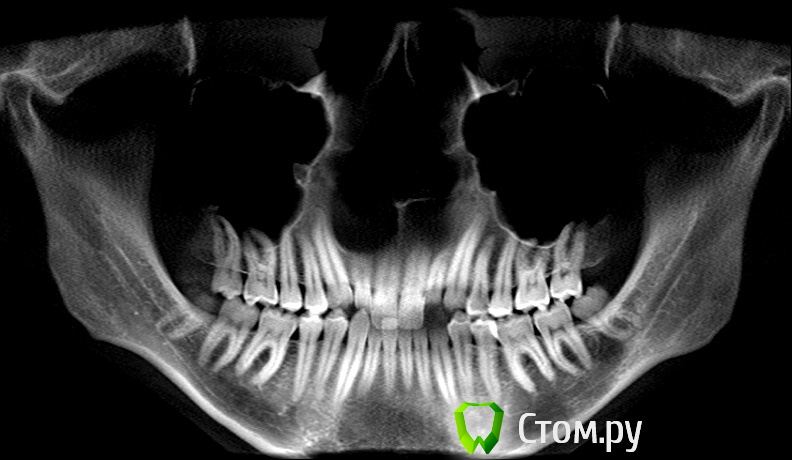

Здравствуйте! Мне 27 лет.  Очень вас прошу дать свою оценку моей ситуации. У меня сложная ситуация, я уже обошел многие ортодонтические кабинеты своего города и все говорят разное. У меня мезальный прикус, но своим профилем я доволен, я всем доволен, кроме того что у меня неправильный прикус (верхние резцы заходили за нижние и были вогнуты вовнутрь) и кривые зубки.Сейчас по рекомендации одного ортодонта ношу капу чтобы верхние резцы перепрыгнули, но теперь и это занятие меня сильно беспокоит, хотя ношу всего месяц и уже попадает зуб на зуб. Главный мой вопрос таков: "Возможно ли в моей ситуации исправить прикус без операции?" Спасибо за ответы!

можно, еще ТРГ надо,